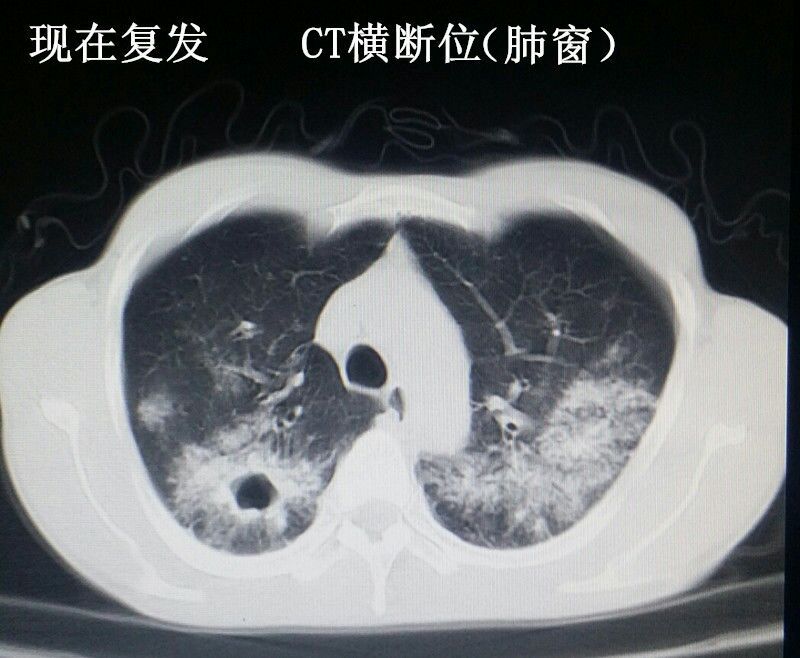

男性青年,未婚。 主诉:咳嗽数月,发现血尿三天。 现病史:患者半年前出现咳嗽症状,自服“消炎药”可减轻,一直未愈,近来加重。右腰背部偶感不适。发现终末血尿三天。患者自述近来消瘦、乏力。精神可,饮食可,睡眠好。 既往史:患者四年前因粟粒性肺结核就诊于当地结核病医院,给予口服抗结核治药物治疗(具体药物不详),后复查未见明显异常。 个人史:吸烟十年。 婚育史:未婚。 家族史:父母体健,无遗传病史。 实验室检查:肌酐:200umol/L(59-104) 尿素:10.4umol/L(2.86-8.2) 本院非结核病防治医院,无结核相关实验室检查。其余检查无阳性发现。 影像学检查(见插图): 1.四年前胸部平片及CT显示:双肺密布粟粒样结节,考虑肺结核。 2.现在胸部CT示:右肺尖及双肺背侧可见片状不规则高密度影,右肺中叶见厚壁空洞。考虑空洞型肺结核。 3.现在行腹部立位平片及CT示:右肾呈高密度团块状,结合病史考虑肾自截。 4.为进一步明确分肾功能,行核素肾动态显像示:右肾未见明显血流灌注,右肾未见明显显影,右肾功能重度受损,右肾肾图呈低水平延长线性改变。左肾功能大致正常。 诊疗经过:鉴于右肾无功能,行右肾摘除术(送病理,回报:肾结核)。请胸外科会诊,建议转入胸外科行肺段切除术。目前右肾摘除术后。 小结:近年来结核病例有上升趋势,尤其是肺结核。本病例类似的情况较少见,特此分享供大家学习。